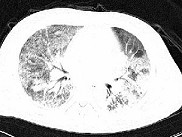

单项选择题男性,42岁, 近2年来无明显诱因反复出现咳嗽,痰少, 活动后气促,无发热, 无胸痛,无咯血, 心电图及心脏彩超未见异常,肺功能FEV1.901, FVC2.001,DLco下降, 支气管激发试验阴性。胸部CT见图,该患者最有可能是下列哪一种疾病 ( )

E、特发性间质性肺炎